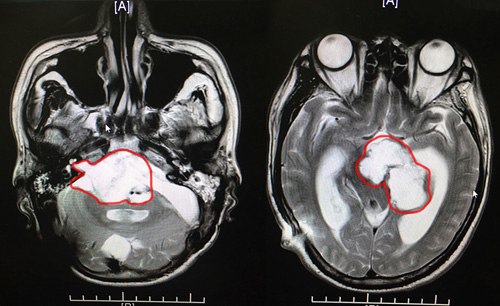

沈教授说:根据患者在蓝十字做的核磁检查报告,我们发现环池、桥前池,鞍上池,左侧四叠体池占位,很有可能是肿瘤术后残余。而且患者的左侧后颅窝硬膜下和左侧枕骨头皮下都是积液,这个情况是必须要再做手术了。

患者术前影像:环池、桥前池,鞍上池,左侧四叠体池占位